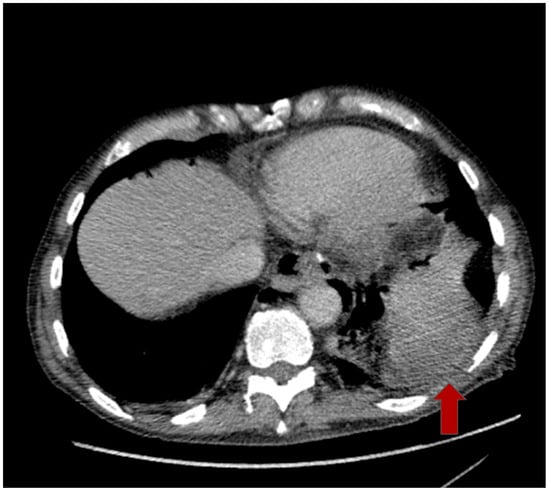

2.2. Multimodal Approach and Treatment

2.3. Postoperative Course